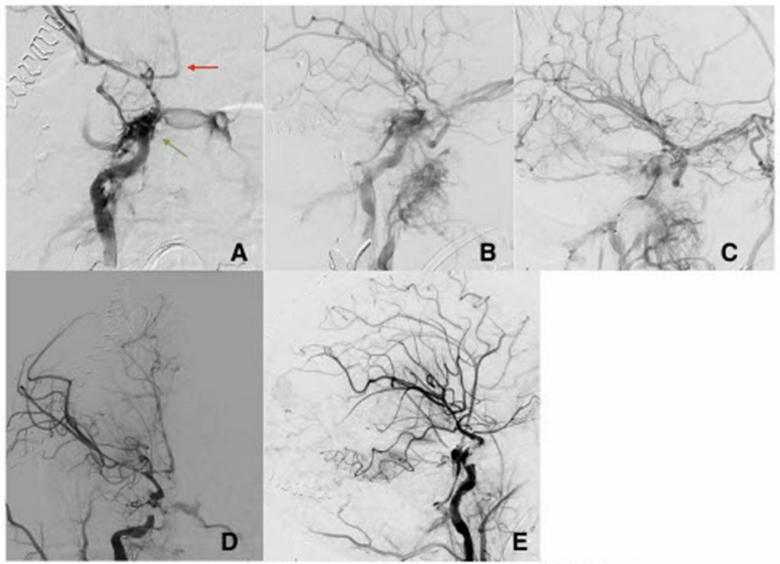

在随后的几个小时里,对患者进行了紧急减压半颅骨切除术,并放置了右侧龈下引流管。三天后,由于血流动力学稳定,常规脑血管造影显示右侧tCCF高流量,皮质静脉明显动脉化。通过经静脉途径栓塞tCCF,显著减少瘘流(图1A~C)。

栓塞七天后,患者出现右瞳孔固定性散瞳。常规脑血管造影术显示tCCF保持通畅,右眼浅静脉、双侧海绵窦、翼丛和岩下窦血流明显。经过多学科讨论后,在海绵窦段的瘘管上部署了分流支架,随后动静脉分流显著减少(图1D,E)。

图1. AP视图(A)和侧视图(B),右侧ICA海绵窦段和海绵窦之间有直接瘘(绿色箭头)。颅内有严重血管痉挛的证据(红色箭头)。(C)瘘管部位部分卷绕后的斜视图。(D)右ICA分流支架和螺旋后的AP图和侧视图(E),CCF改善,颅内血流改善